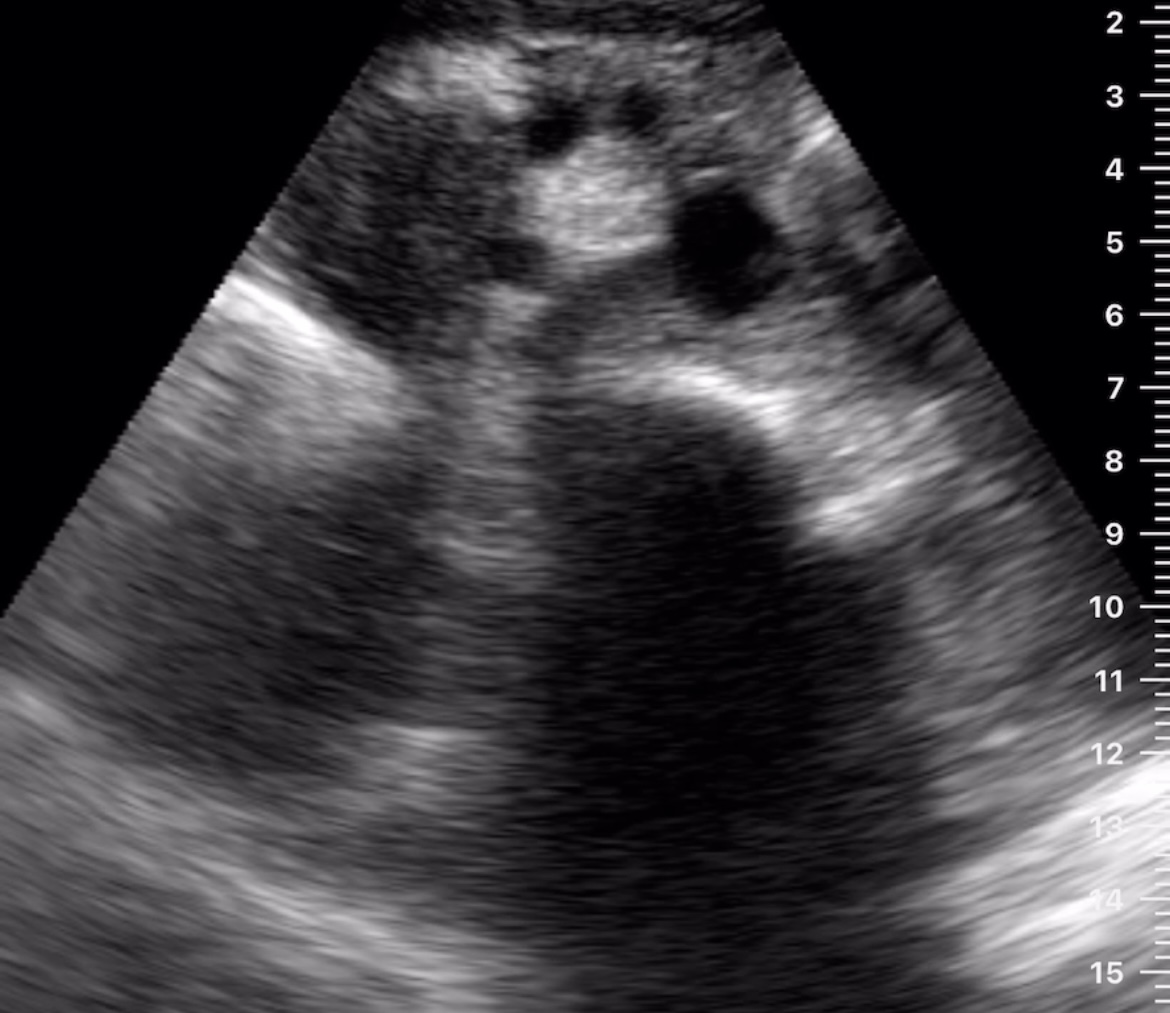

Hallazgos ecográficos

Observamos una lesión a nivel de la cabeza del páncreas, de bordes mal definidos, hipoecogénica, además de dilatación del conducto de Wirsung y dilatación de la vía biliar tanto intra como extrahepática.